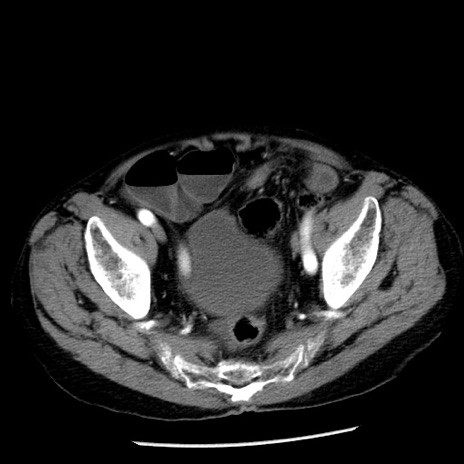

症例26(横断像)

【症例】80歳代男性

【主訴】嘔吐

【現病歴】昨晩2回嘔吐あり、今朝になっても嘔吐あり。来院。

【既往歴】胃潰瘍

【身体所見】意識清明、BT 37.6℃、BP 166/95mmHg、HR 100bpm、SpO2 97%、腹部:平坦・軟、腸蠕動音聴取良好、圧痛なし。

【データ】WBC 21900、CRP 1.46